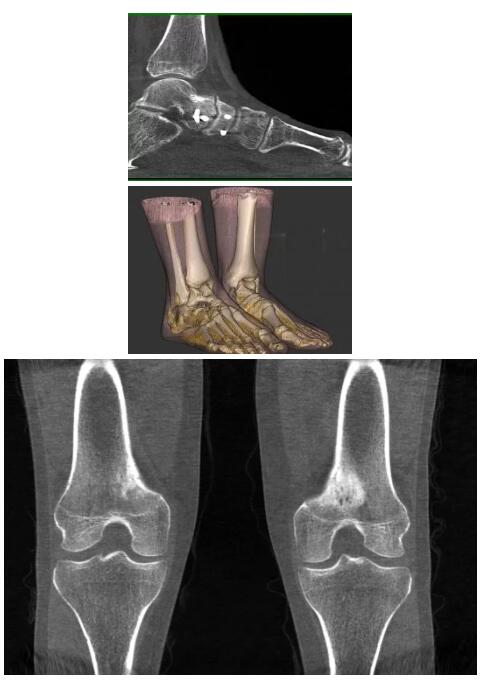

比如上面這款專用于足部和踝部掃查的CT成像系統(tǒng),患者在進(jìn)行CT掃查時(shí)只需要站在上面即可,雙腳站或者單腳站都可以,當(dāng)然,如果患者不是那么方便站著做完CT掃查,也可坐在上面。

這款CT掃查系統(tǒng)自帶屏蔽裝置,它的體積非常小,僅需要極小的空間即可,并不像常規(guī)CT那樣需要一間單獨(dú)的檢查室。此外,這種CT掃查的速度非常快,僅需30秒左右可以完成檢查,輻射劑量相對(duì)常規(guī)的CT要少許多,尤其適合醫(yī)院的骨科使用。

而患者站著做足部或者踝部做CT檢查還有個(gè)好處是,可以檢查患者在負(fù)重的情況下,骨關(guān)節(jié)的真實(shí)情況,而躺著做CT掃查時(shí)未必能看出來。負(fù)重CT掃查特別是對(duì)于受傷的運(yùn)動(dòng)員或者舞蹈員來說意義更大,能夠更準(zhǔn)確地評(píng)估傷情,幫助他們盡早復(fù)原。

以上介紹的CT均來自國(guó)外同一家公司,這些CT均配置了可視化軟件,可以進(jìn)行切片、3D重建以及大型CT附帶的所有典型的操作功能。

以下是這些“特立獨(dú)行”的CT所拍出來的圖像: